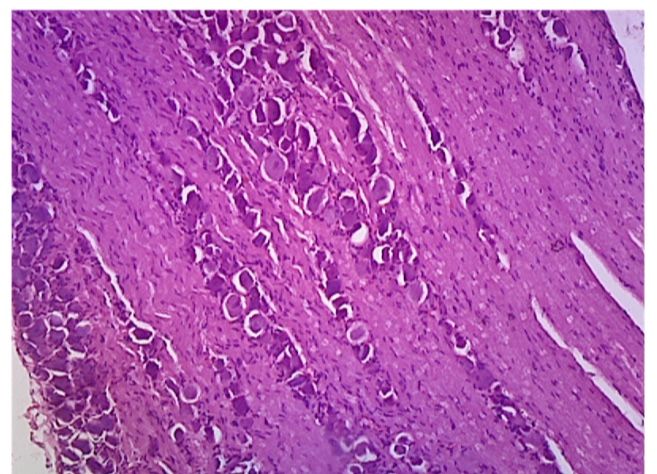

Evaluation of Oxidative Stress and Histoarchitecture of the Pituitary Gland in Male Wistar Rats Exposed to Tramadol and Vitamin D3 Supplementation.

Evaluation of Histomorphological Changes in Liver of Cadmium Induced Hepatotoxicity in Wistar Rats Treated With Sour Sop Leaf Extract

Effect of Oral Administration of Myristica Fragrans(nutmeg) on the Kidney of an Adult Male Wistar Rat

Effect of Chronic Sleep Deprivation on the Histological Architecture of the Heart of Rats With Peptic Ulcer'